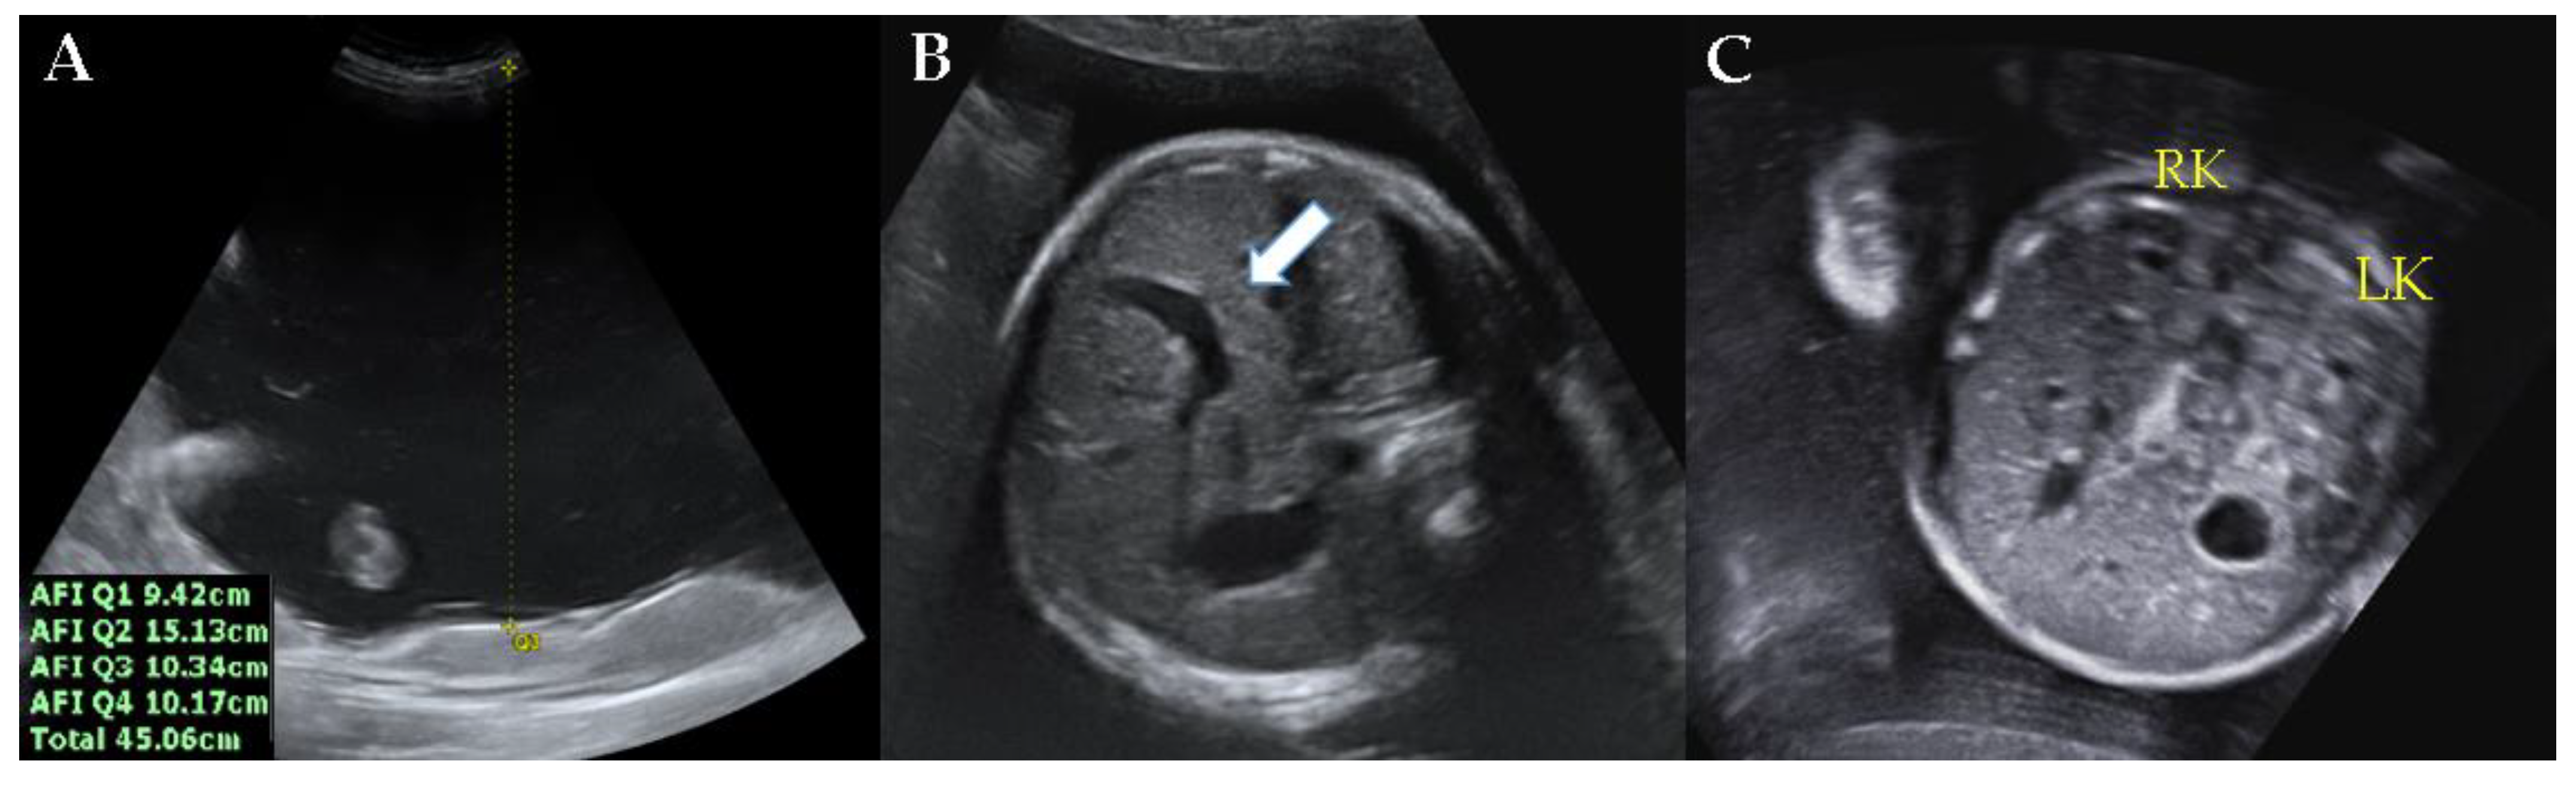

2. Case